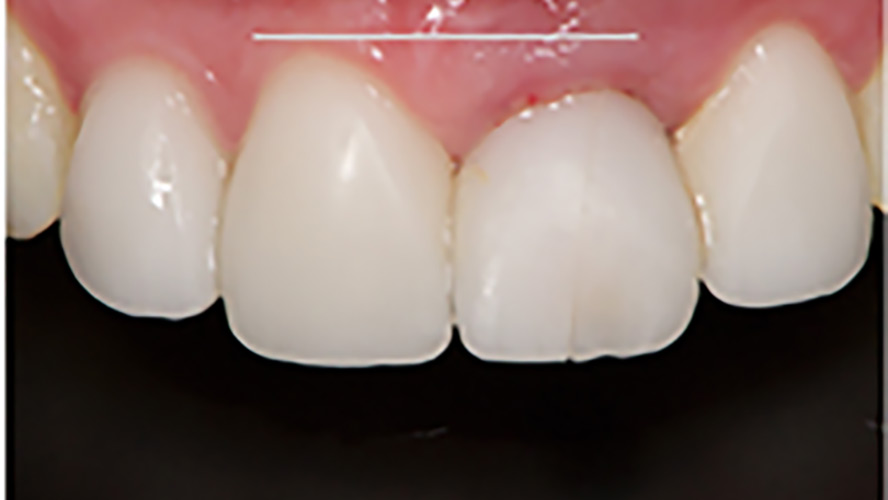

Simplifying Anterior Restorations in Aesthetic Implant Dentistry

The dental implant is a prosthetic device delivered through a surgical process. It allows clinicians to replace one or multiple missing teeth without damaging the remaining dentition. Many attempts have been made in the literature to define the success, failure, and the factors that will influence the outcome. As clinicians, our focus should be on … Read more